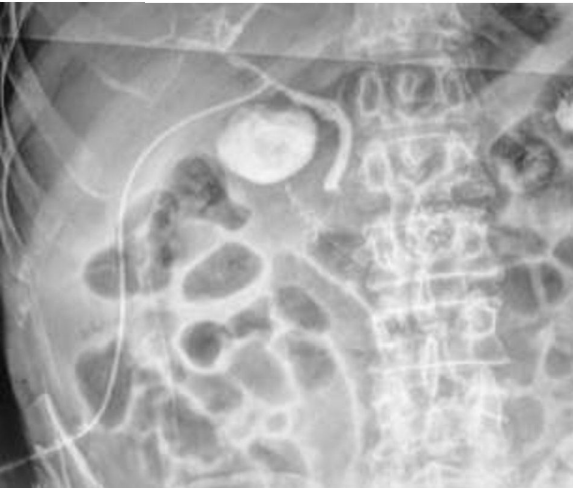

MJS. 29 anos. Submetida a procedimento cirúrgico hepatobiliar há 1 semana. Submetida à imagem complementar abaixo:

Enunciado 3531514-1

Qual exame foi realizado?